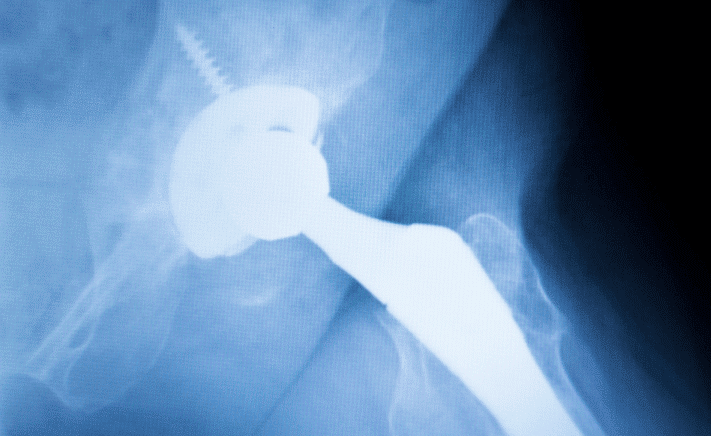

Johnson & Johnson and its subsidiary, DePuy Orthopaedics, have a long history of harming patients through their defective hip implants. The pharmaceutical liability attorneys at The Lanier Law Firm stand up to large pharmaceutical companies on behalf of innocent individuals.

Harm Caused by DePuy’s Hip Implants

DePuy/J&J’s hip implants were constructed with a metal-on-metal design, which, when rubbed together, could create metal shavings. According to the FDA, these shavings can cause the following issues: